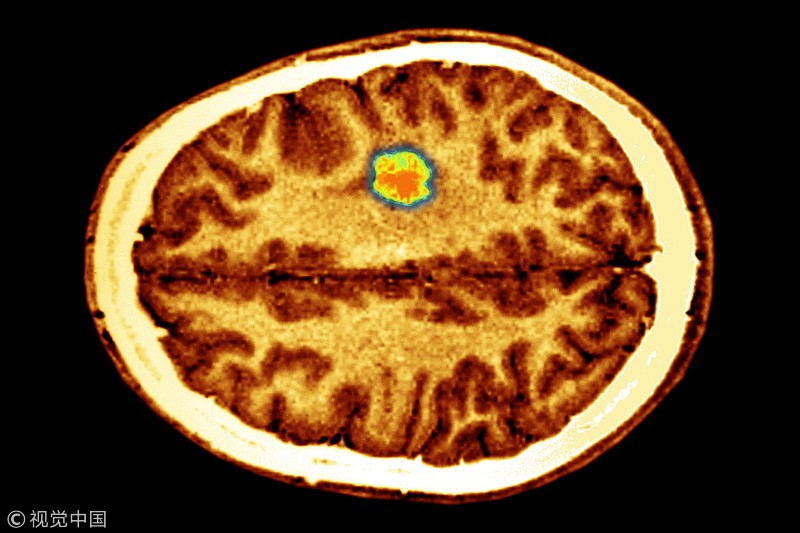

Glioblastoma (GBM) is the most common and malignant form of primary brain tumor. Treatment with surgery, radiation and chemotherapy has limited effect, and the recurrence rate is almost 100 percent. The average survival time of patients is about 14 months.

Scientists said they have developed a Zika virus vaccine that can inhibit brain tumor growth. /VCG Photo